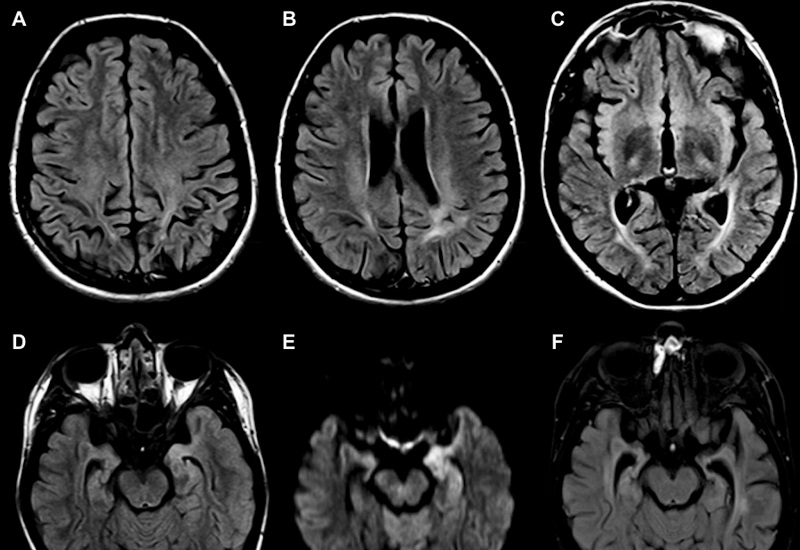

3.1. Hình ảnh chụp MRI giúp phát hiện các bệnh lý về não

MRI đóng vai trò quan trọng trong việc phát hiện các bệnh lý não bộ như u nang, khối u, xuất huyết, phù nề và các cấu trúc bất thường khác. Ngoài ra, phương pháp này còn giúp chẩn đoán các tổn thương do chấn thương sọ não, đột quỵ hoặc các bất thường về mạch máu như thông động tĩnh mạch. Những kỹ thuật tiên tiến như MRI tưới máu, MRI phổ và MRI đánh giá sợi trục thần kinh giúp phân tích chuyên sâu, hỗ trợ phát hiện sớm và chính xác các bệnh lý thần kinh.

Đặc biệt, MRI mang lại hình ảnh nhu mô não rõ nét, giúp phát hiện các bệnh lý mãn tính của hệ thần kinh mà các phương pháp như X-quang, CT hay siêu âm khó có thể quan sát được. Phương pháp này cũng có độ chính xác cao trong chẩn đoán các bệnh lý liên quan đến tuyến yên và thân não, giảm thiểu nguy cơ bỏ sót tổn thương quan trọng.

MRI đóng vai trò quan trọng trong việc phát hiện các bệnh lý não bộ